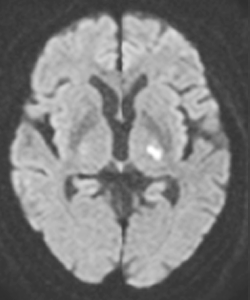

②脳梗塞には大きく3つのタイプに分かれます。そして、それぞれ治療法が異なります。脳の深部にある細い動脈がつまるラクナ梗塞、脳血管の動脈硬化に起因するアテローム血栓性脳梗塞、心房細動といった不整脈などの心疾患のために心臓の中で血栓ができて、それが脳に流れていってつまる心源性脳塞栓症の3つのタイプです。MRI検査は、3つのタイプを鑑別するために重要な検査です。MRI検査により、脳のどの部分が、どの程度梗塞に陥っているかを明らかにします。

ラクナ梗塞

心源性脳塞栓症